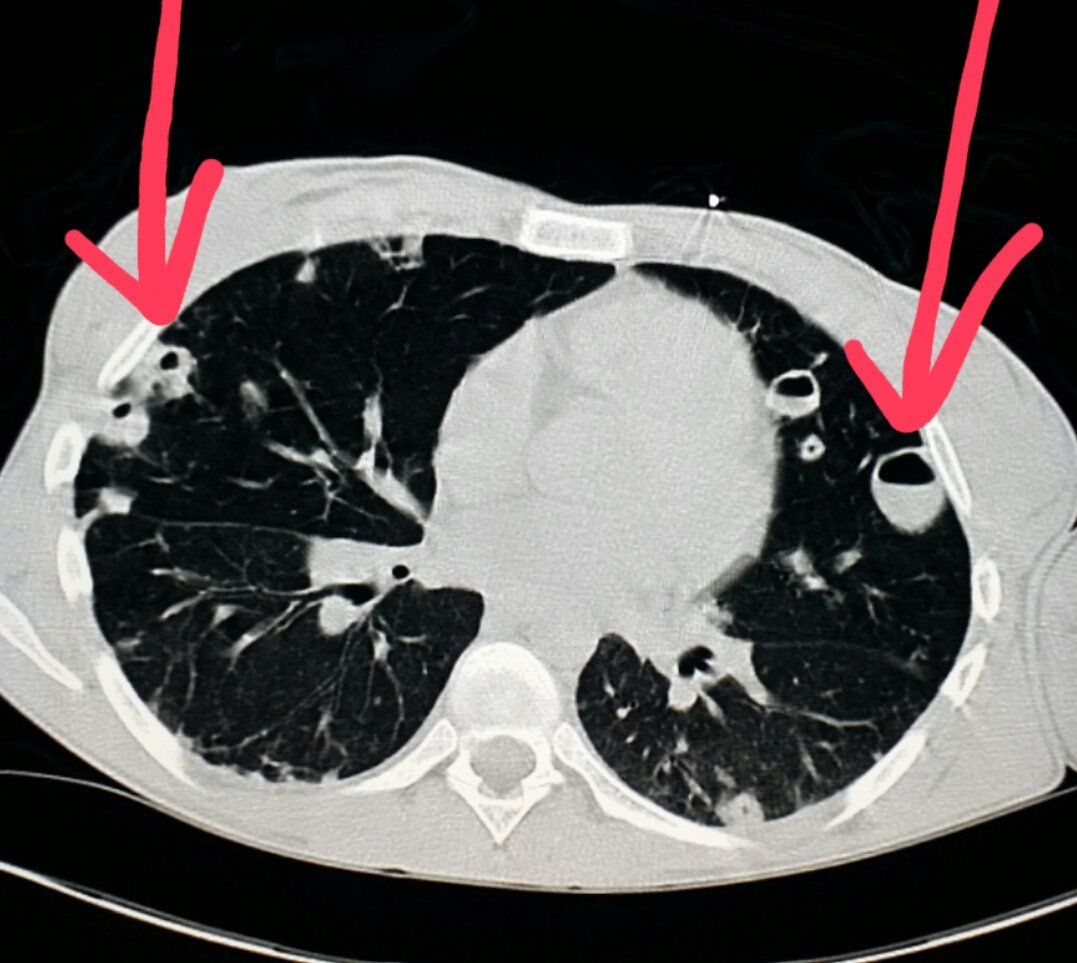

A lung nodule (or pulmonary nodule) is a small, round or oval-shaped growth in the lungs that is up to 3 centimeters in diameter. A lung nodule larger than 3 centimeters is called a lung mass. Lung nodules are common, mostly in those who smoke, and are typically benign (non-cancerous) but can also be malignant (cancerous). You may have a single lung nodule or several.

To start, your doctor will discuss your medical history with you, perform a physical exam and a chest X-ray or CT scan. These scans can help your doctor see the size, shape and location of the lung nodule, as well as other characteristics, like calcium deposits. From there, they may recommend additional tests to rule out cancer or to determine another underlying cause. These can include:

A lung nodule (or pulmonary nodule) is a small, round or oval-shaped growth in the lungs that is up to 3 centimeters in diameter. A lung nodule larger than 3 centimeters is called a lung mass.

Lung nodules are common, mostly in those who smoke, and are typically benign (non-cancerous) but can also be malignant (cancerous). You may have a single lung nodule or several.

A lung nodule (or mass) is a small abnormal area that is sometimes found during a CT scan of the chest. These scans are done for many reasons, such as part of lung cancer screening, or to check the lungs if you have symptoms.

Most lung nodules seen on CT scans are not cancer. They are more often the result of old infections, scar tissue, or other causes. But tests are often needed to be sure a nodule is not cancer.

Most often the next step is to get a repeat CT scan to see if the nodule is growing over time. The time between scans might range anywhere from a few months to a year, depending on how likely your doctor thinks that the nodule could be cancer. This is based on the size, shape, and location of the nodule, as well as whether it appears to be solid or filled with fluid. If a repeat scan shows that the nodule has grown, your doctor might also want to get another type of imaging test called a positron emission tomography (PET) scan, which can often help tell if it is cancer.

CT diagnosis of pulmonary fibrosis

The gold standard for diagnosing pulmonary fibrosis is high-resolution computed tomography. CT diagnostics of pulmonary fibrosis allows to reliably identify the degree of lung damage, to determine the localization of scar tissue. This diagnostic method is recognized as one of the most sensitive non-invasive methods for detecting pulmonary fibrosis. Thus, comparative studies conducted already in 1990 showed that pulmonary fibrosis using high-resolution computed tomography (HRCT) was detected in 91% of cases and only 39% using chest x-ray.

In the presence of pulmonary fibrosis in a serious stage, a pattern (a term adopted for pathological signs in medicine) is visible on CT scans of the so-called “honeycomb” lung – this condition is visible on scans as the same type of air-containing cysts located in several rows in the affected parts one or both lungs. In the early stages of pulmonary fibrosis, such a picture is not observed, so it was necessary to look for signs on CT that would allow to identify the disease at its onset.

One of these signs was the presence of a “ground glass” pattern in the images – foci of slight compaction of the lung tissue. Also, specific signs of fibrosis in a patient can be detected when performing a CT scan of the lungs with functional tests. So, one of the signs – subpleural enhancement of the peripheral pulmonary interstitium – was previously considered a sign of the absence of pathology. Such changes are almost impossible to track using other methods of hardware diagnostics.